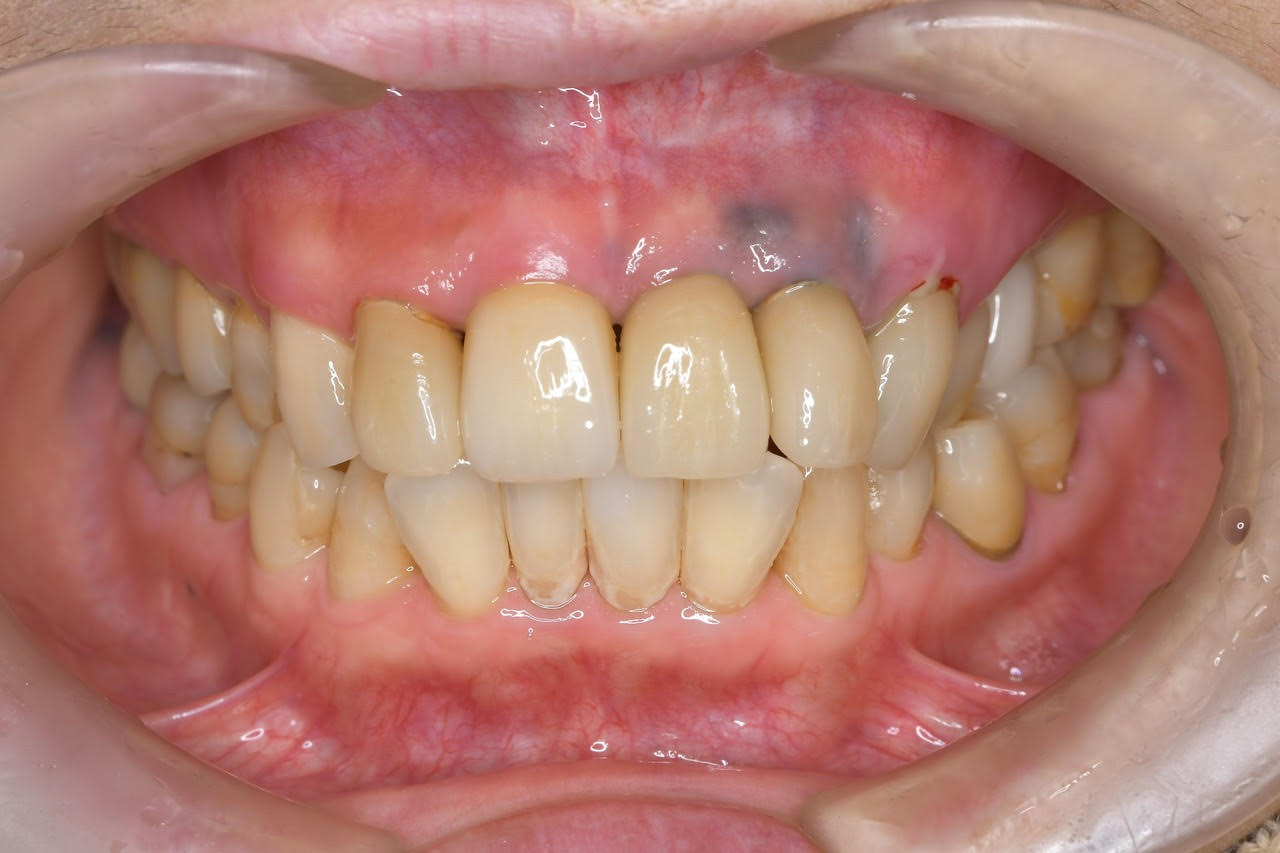

完成した前歯は、天然の歯と見分けがつかないほど自然な仕上がりとなりました。

患者さんからは、「孫との遊びもまた思い切り楽しめるようになりました。1年もかかると言われていたら諦めていたかもしれませんが、数ヶ月で、しかも手術が1回で済んで本当に良かったです」とのお言葉をいただきました。